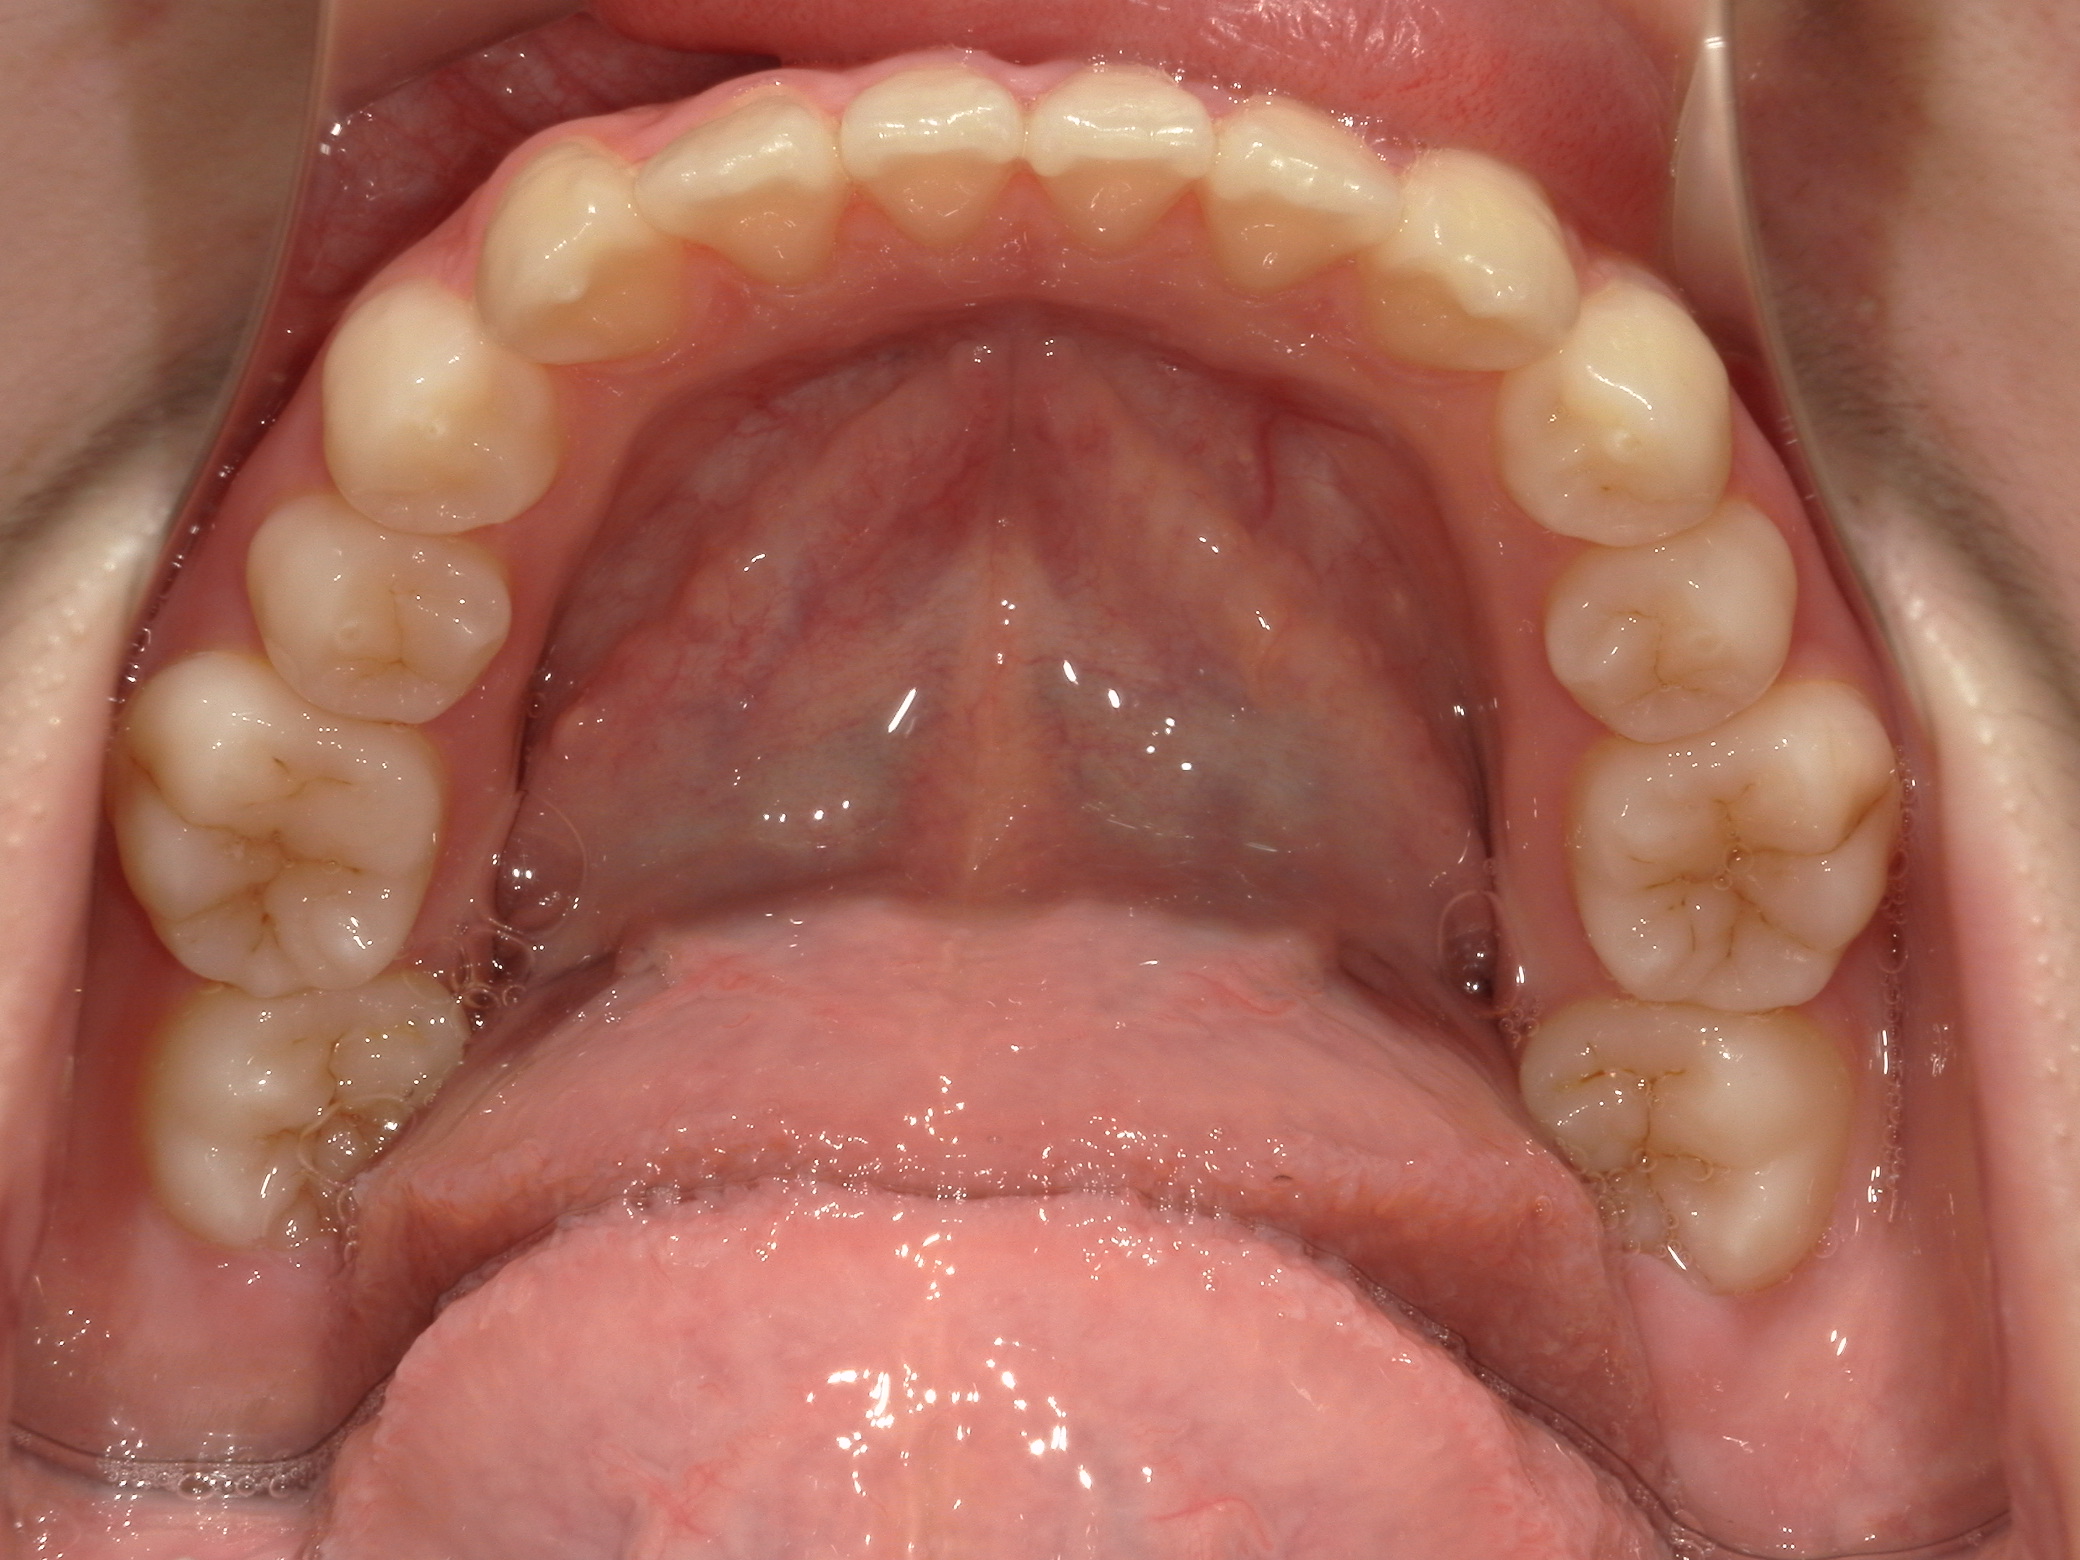

この症例の気になるの点として、無理な拡大で下顎左右6番の歯根が頬側の皮質骨からはみ出ている危険があることです。そうならば、下顎6番の近心移動はものすごく遅くなります。等と考えていたので、当然のごとく抜歯部位の選定に悩みました。悩んだ末、この症例は上下左右の6番抜歯症例です。

上顎の咬合面は写真の撮り忘れで、模型の咬合面観で代用しています。